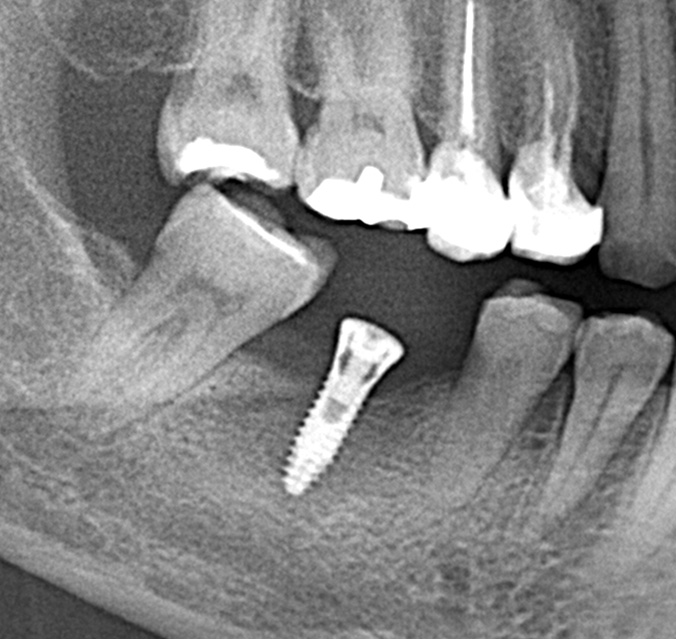

インプラント手術を行いました。

手術の時に使用するサージカルステント

レントゲン画像 -